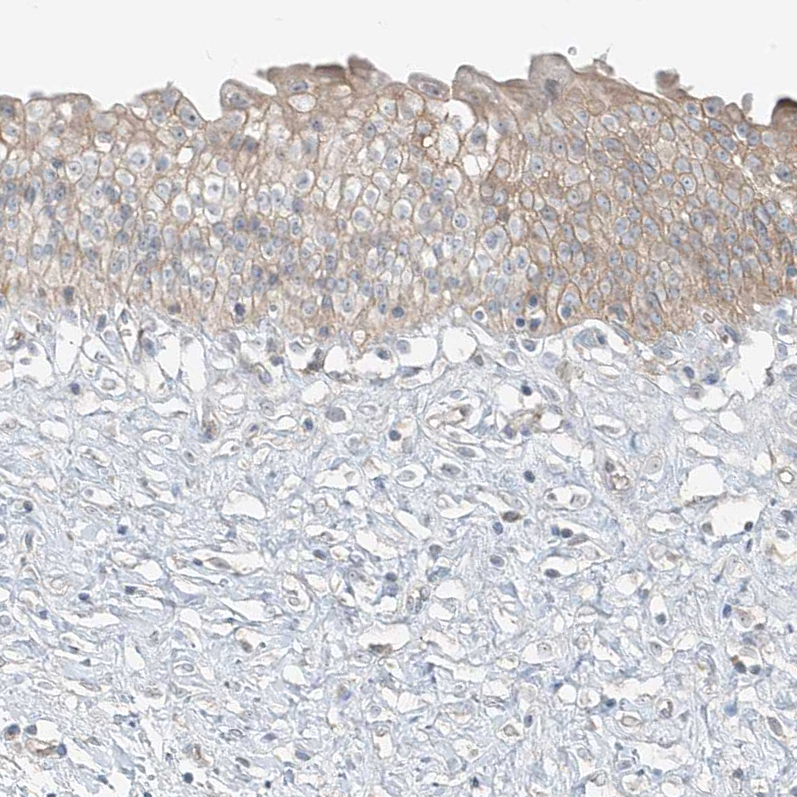

Immunohistochemical staining of human testis shows moderate cytoplasmic positivity in Leydig cells.